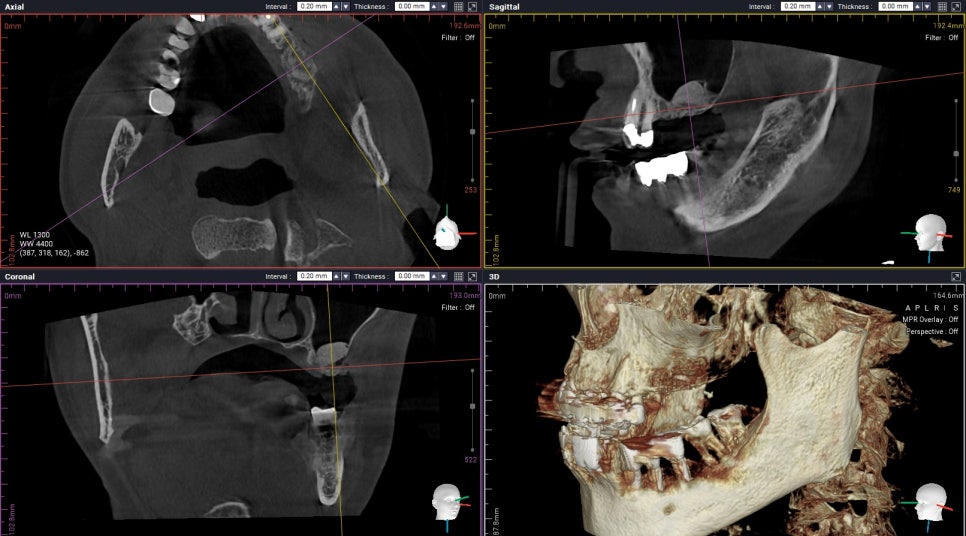

Sinus Augmentation Teeth No. 13,14,15

As always,

원장님은

수술 중에

3D CT를 통해

상악동막이 찢기지는 않았는지,

뼈이식 양과 높이는 제대로 올라가는지

꼭 체크합니다. :)

(세번째 케이스)

Periodontally involved teeth

Following implant placement with sinus graft

이 환자분의 경우

우측 위 어금니를 발치하고나서

충분히 기다린 후

수술을 진행 하셨는데요,

염증이 있던 치아 였기에

뼈이식을 충분히 하고

수술을 진행했습니다 :)

Confirmation with CBCT